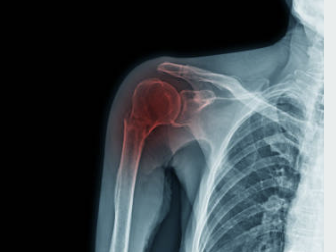

어깨 회전근개는 상완뼈와 견갑골 사이에 위치한 네 개의 근육과 그 근육들을 연결하는 건으로 이루어진 구조입니다. 이는 상체를 움직이는 데 있어서 중요한 역할을 합니다. 어깨 회전근개는 팔을 들거나, 회전하거나, 상체를 앞으로 내밀 때 근육을 동원하여 이를 가능하게 합니다. 어깨 회전근개는 근육과 건으로 이루어져 있기 때문에 손상이 발생하면 회복이 어렵습니다.